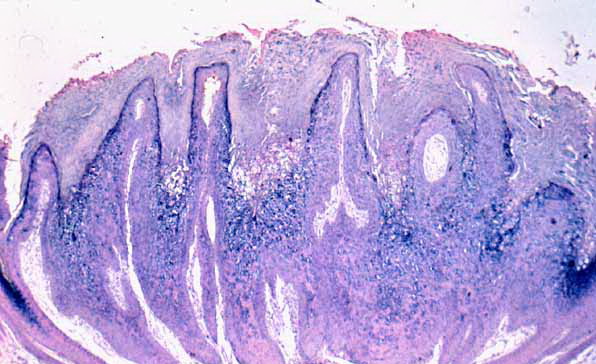

Verruca vulgaris = الثؤلول الشائع